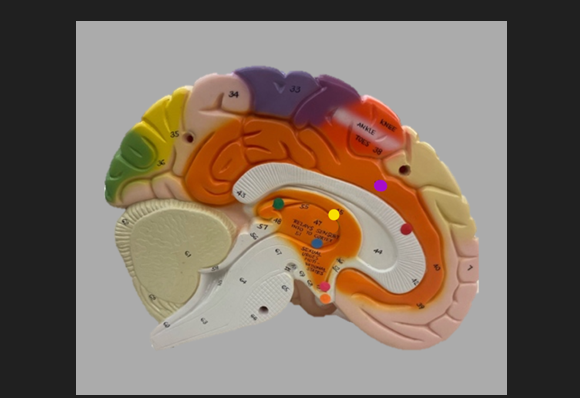

frontal lobe

blue dot

longitudinal fissure

dark green dot

precentral gyrus

pink dot

postcentral gyrus

yellow dot

central sulcus

white dot

parietal lobe

light green dot

Broca’s Area

red dot

Wernicke’s Area

orange dot

occipital lobe

blue dot

parieto-occipital sulcus

blue dot

olfactory tract

red dot

corpora quadrigemina

dark green dot

cerebral aqueduct

blue dot

cerebral penduncles

pink dot

pons

orange dot

medulla oblongata

yellow dot

mammillary body

red dot

corpus callosum

dark green dot

pineal gland

yellow dot

epithalamus

blue dot

thalamus

orange dot

optic chiasm

pink dot

infundibulum

purple dot

cingulate gyrus

yellow dot

pituitary gland

dark green dot

pyramids

red dot

olives

blue dot

optic tract

purple dot

midbrain

green dot

folia

orange dot

arbor vitae

yellow dot

fourth ventricle

red dot

vermis

blue dot

hypothalamus

pink dot

cerebral hemispheres

yellow dot

lateral sulcus

red dot

lateral ventricles

blue dot

hippocampal gyrus